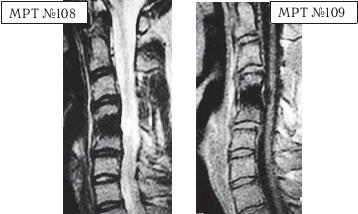

МРТ № 1

На магнитно-резонансной томографии (МРТ) № 1 — шейный отдел позвоночника, в относительно нормальном состоянии.

Шейный отдел позвоночника должен иметь нормально выраженный физиологический лордоз, не должно быть гиполордоза или гиперлордоза, а так же кифотических деформаций.

Ширина спинного мозга: сагиттально > 6–7 мм

1. Сагиттальный размер позвоночного канала на уровне:

СI 21 мм

СII 20 мм

СIII 17 мм

CIV-CVII = 14 мм

2. Высота межпозвонковых пространств:

СII < СIII < СIV < СV < СVII  СVII

3. Ширина спинномозгового канала: поперечный диаметр на уровне ножек: > 20–21 мм